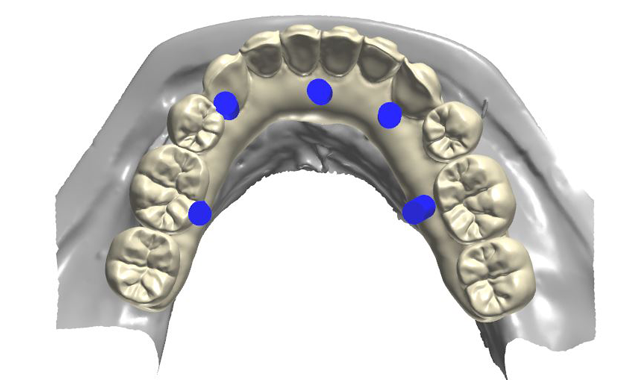

The wax set-up was scanned and digitized to fabricate a poly-methylmethacrylate (PMMA) restoration (Figs. 9-10). The design software for the aforementioned scanner had the ability to uniformly cut back the gingival area of the prosthesis to a desired thickness so space would be provided to apply tissue-colored composite resin to esthetically simulate soft tissue (Figs. 11-11b). After milling the PMMA blank, tissue-colored composite (Gradia, GC International) was applied and subsequently finished and polished. The esthetics, lip support and occlusion were then confirmed intraorally.

Fig. 9

Fig. 10

Fig. 11

Fig. 11b